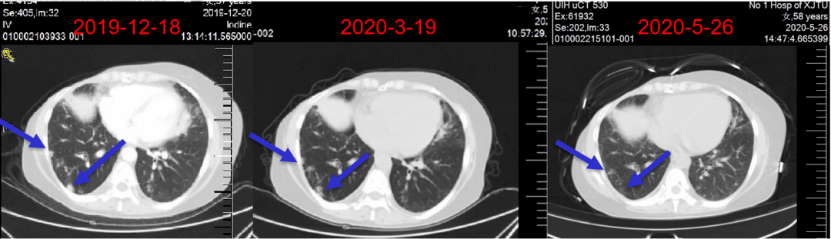

病情演变:2019年12月18日,随访影像学显示肝脏转移病灶可能(图8)。

图8:一线治疗期间随访肝脏及肺部病情演变